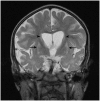

Migrating partial seizures of infancy, also known as epilepsy of infancy with migrating focal seizures, is a rare early infantile epileptic encephalopathy with poor prognosis, presenting with focal seizures in the first year of life. A national surveillance study was undertaken in conjunction with the British Paediatric Neurology Surveillance Unit to further define the clinical, pathological and molecular genetic features of this disorder. Fourteen children with migrating partial seizures of infancy were reported during the 2 year study period (estimated prevalence 0.11 per 100,000 children). The study has revealed that migrating partial seizures of infancy is associated with an expanded spectrum of clinical features (including severe gut dysmotility and a movement disorder) and electrographic features including hypsarrhythmia (associated with infantile spasms) and burst suppression. We also report novel brain imaging findings including delayed myelination with white matter hyperintensity on brain magnetic resonance imaging in one-third of the cohort, and decreased N-acetyl aspartate on magnetic resonance spectroscopy. Putaminal atrophy (on both magnetic resonance imaging and at post-mortem) was evident in one patient. Additional neuropathological findings included bilateral hippocampal gliosis and neuronal loss in two patients who had post-mortem examinations. Within this cohort, we identified two patients with mutations in the newly discovered KCNT1 gene. Comparative genomic hybridization array, SCN1A testing and genetic testing for other currently known early infantile epileptic encephalopathy genes (including PLCB1 and SLC25A22) was non-informative for the rest of the cohort.